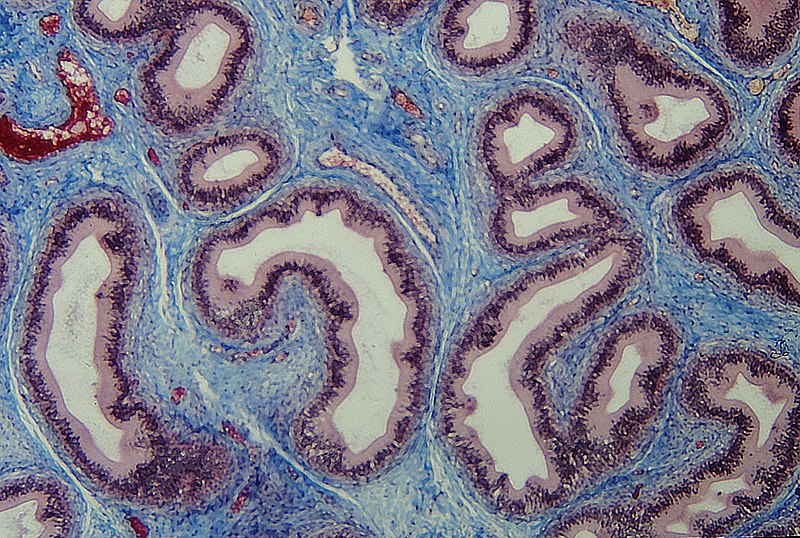

قیمت: 32٬000 تومان - دسته بندی فایل: پاورپوینت

قیمت: 32٬000 تومان - دسته بندی فایل: پاورپوینتپاورپوینت بافت همبند

فروش ویژه پاور پوینت حرفه ای بافت همبند با تخفیف استثنایی فقط 49 هزار تومان تعداد اسلاید: 12 اسلاید